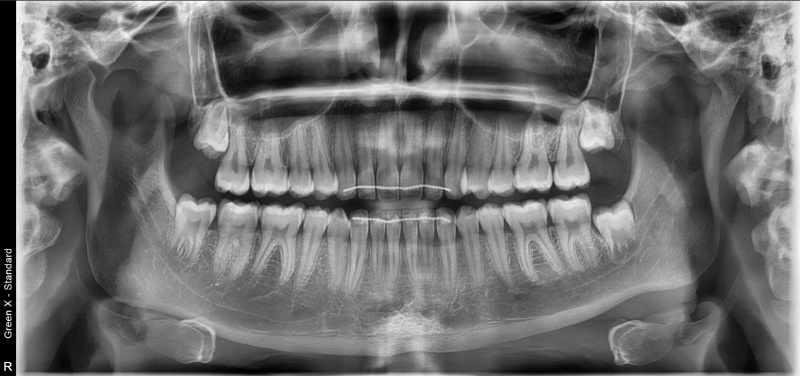

Dokładne obrazy 2D i 3D – niezbędne w chirurgii, ortodoncji, endodoncji i laryngologii

Zakres obrazowania – od pojedynczego zęba po całą czaszkę

Zdjęcie panoramiczne pokazuje całe uzębienie i kości szczęki oraz żuchwy, ujawniając zmiany niewidoczne na RTG punktowym (torbiele, guzy, zapalenia, zwyrodnienia stawów). To badanie profilaktyczne, zalecane co 2 lata.